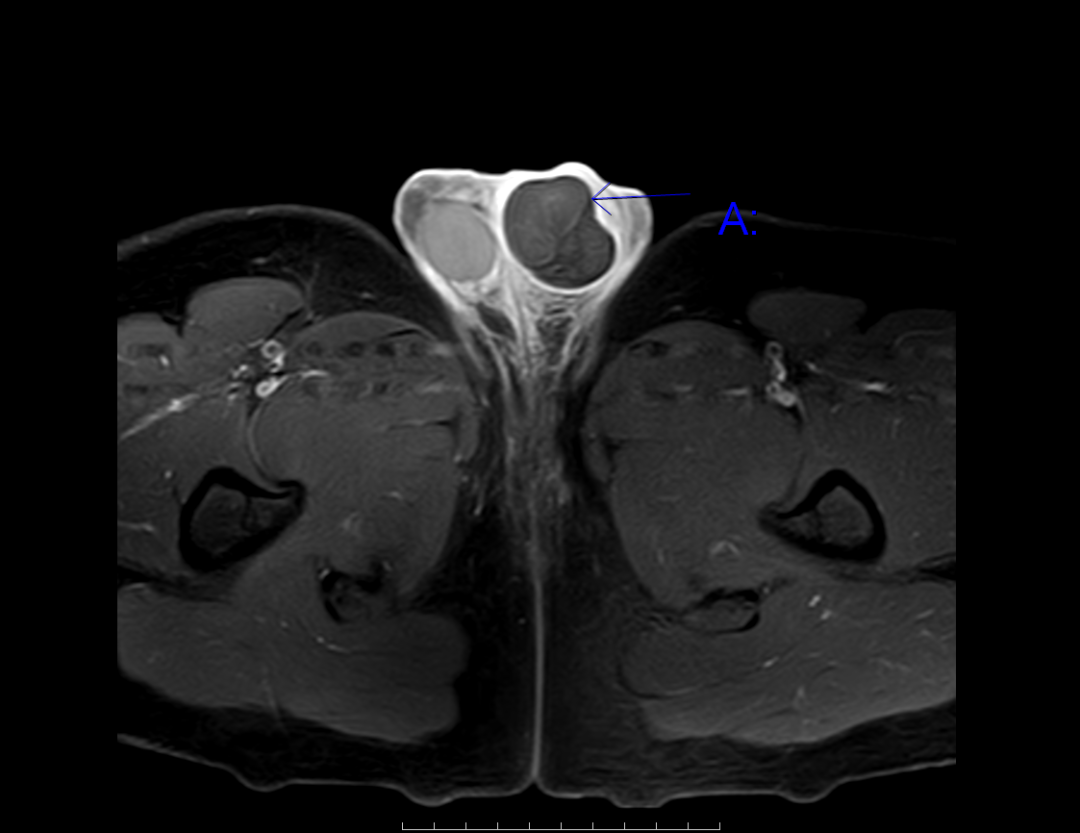

立即完善检查,左侧睾丸完全没有血流信号,精索扭转的影像清清楚楚,这结果所有人都捏了把汗。

“立刻手术!”当手术刀划开阴囊时,所有人都沉默了,连接睾丸的精索足足扭转了 720°,像拧干的毛巾一样绞在一起,原本粉红的睾丸已经变成了深黑色。